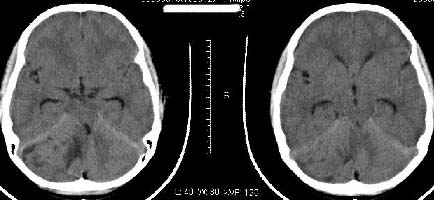

以下是引用子期在2009-6-10 21:34:00的发言:[br]髓母细胞瘤一般位于中线附近和小脑蚓部,该病灶位于右侧小脑半球,倾向于毛细胞型星形细胞瘤,当然也不能完全排除髓母细胞瘤。

以下是引用随光逐影在2009-6-10 22:26:00的发言:[br]考虑右侧小脑胶质瘤,髓母细胞瘤待排。

以下是引用影象小泰斗在2009-6-10 22:14:00的发言:[br]年龄及影像表现军符合小脑星形细胞瘤表现![br]期待病理结果!